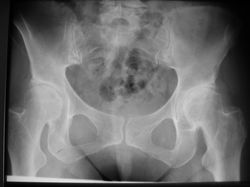

![]() HWS OsteochondroseDegenerative Veränderungen der Halswirbelsäule, Verschleiß | ![]() Coxarthrose bei HüftdysplasieMangelhafte angeborene Überdachung der Hüftköpfe, zu steile Schenkelhalsstellung, daraus entstandene Coxarthrose | ![]() Arteriosklerose Unterschenkel | ![]() Arteriosklerose Unterschenkel 02 |